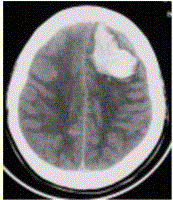

问题 患者男,45岁,突发剧烈头痛伴呕吐30min。既往有高血压病史,平日血压为(190~160)/(100~110)mmHg。查体:右侧肢体肌力Ⅱ级,无颈项强直。CT表现如下图。 关于脑血肿典型的MRI表现,描述不正确的是

选项 A.3d以内,T1WI等信号,T2WI低信号 B.3~6d,T1WI低信号,T2WI低信号 C.6~8d,T1WI高信号,T2WI高信号 D.15d以后,T2WI上高信号的血肿周围出现低信号环 E.完全液化后,T1WI低信号,T2WI高信号

答案 B